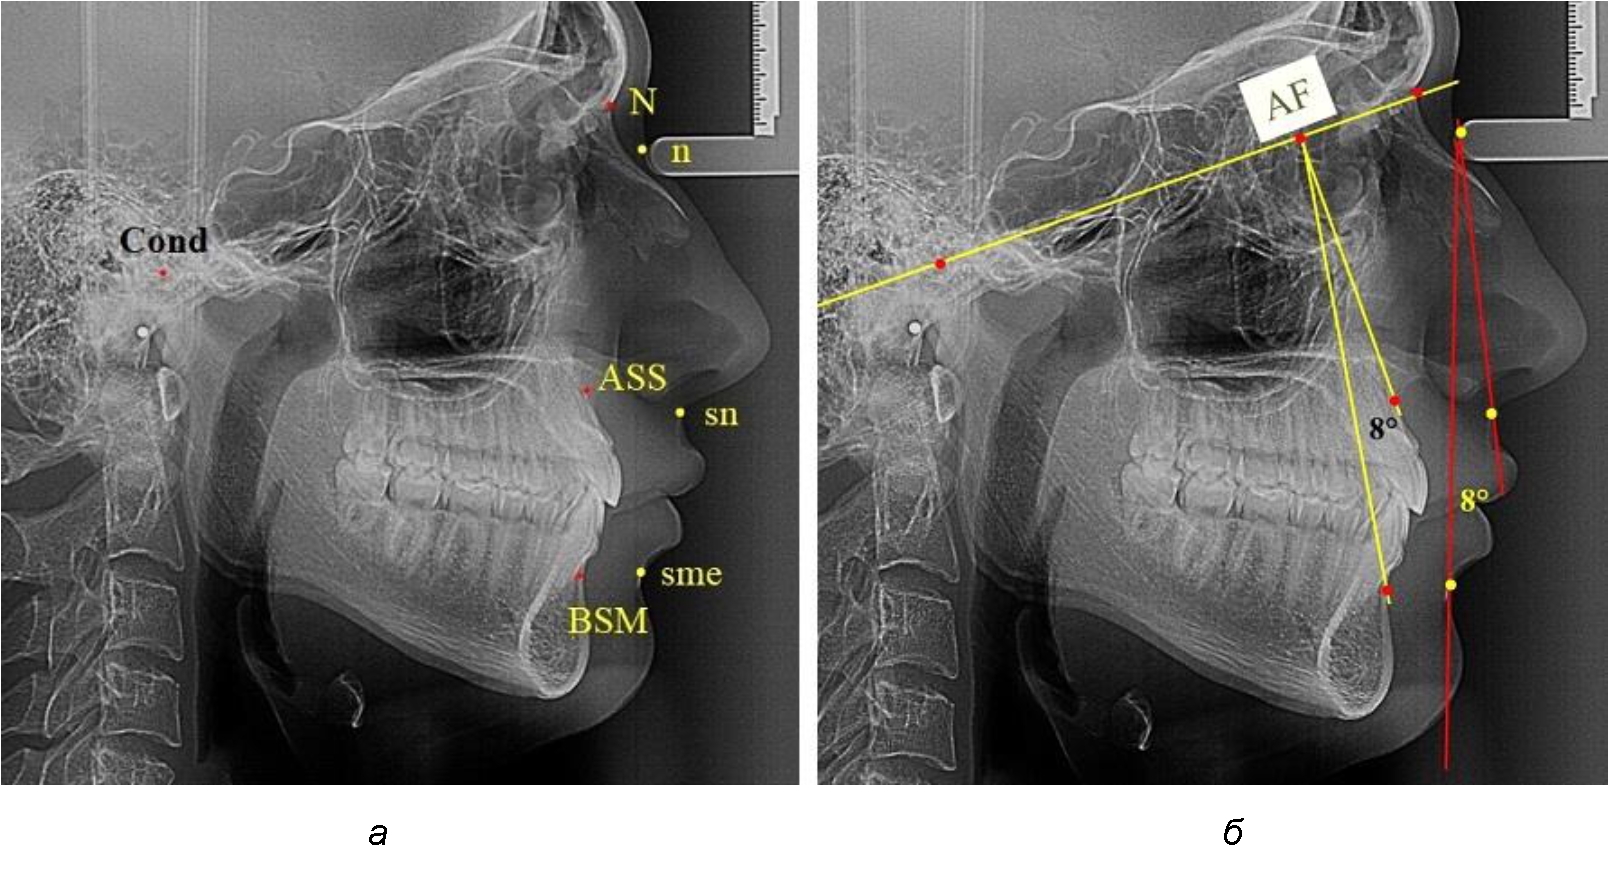

Лицевой межгнатический угол по кожным ориентирам строили соединением точек sn-n-sme, который обозначали как назально-супраменталь-ный угол (рис. 1).

Рис. 1. Точечные ориентиры (а) и основные линии (б) боковой ТРГ для анализа параметров лицевого межгнатического угла

Для построения лицевого межгнатического угла по костным ориентирам использовали в качестве основного ориентира кондилярно-назальную линию, соединяющую точки Cond (верхняя точка суставной головки) и N (место соединения лобной и назальных котей). На передней поверхности челюстей, в наибольшей вогнутости переднего контура, отмечали апикальные точки Downs (ASS и BSM). Из субспинальной точки Downs верхнего апикального базиса ASS строили перпендикуляр к линии Cond–N. Место пересечения линий определяло положение конструктивной апикально-фациальной точки, которую обозначали литерами AF. Точку AF соединяли с супраментальной точкой Downs (BSM) нижнего апикального базиса. Таким образом, костный лицевой межгнатический угол обозначали как угол ASS–AF–BSM. Для определения типов нижней челюсти оценивали величину нижнечелюстного угла. В исследовании выделяли группы людей с нейтральным, вертикальным и горизонтальным типами, которые влияли на положение нижней челюсти.

При фотостатическом анализе использовали профильные фотографии, на которых обозначали точки переднего профильного контура лица, позволяющие определить кожный лицевой межгнатический угол n–sn–smе, который, так же как и при телерентгенографичесом исследовании, обозначали как назально-супраментальный угол (рис. 2). Угол t–n–sn определял типологические варианты лица. Величина угла в 80° характерна для людей с нормопозицией верхней челюсти. Антепозиция верхней челюсти определялась увеличением угла, а ретропозиция – уменьшением. Данные типы лица также оказывали влияние на положение нижней челюсти. Величину угла нижней челюсти использовали в качестве типологической оценки ее роста.

Рис. 2. Точечные ориентиры (а) и основные линии (б) профильного снимка лица для анализа параметров лицевого межгнатического угла